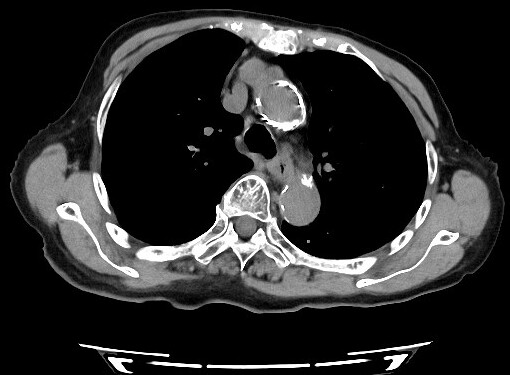

低線量肺CT診断画像1

低線量肺CT診断画像2

低線量肺CT診断画像3

低線量肺CT検査

低線量肺CT検査は、通常のCT検査よりも少ない放射線量で肺の状態を詳しく調べる検査です。

胸部X線検査よりも小さな病変の発見に優れており、肺がんの早期発見に役立ちます。